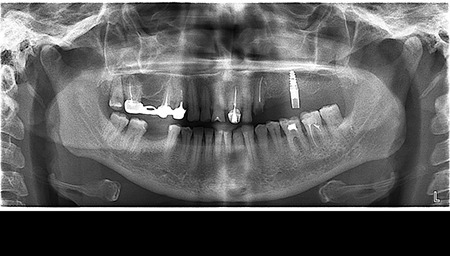

- Цифрова панорамна рентгенографія (ортопантомограма) – дає цілісне зображення всієї щелепно-лицевої системи.

Що ви уявляєте, коли лікар говорить про ортопантомограму? Насправді, це знімок усієї зубощелепної системи, який охоплює обидві щелепи, гайморові пазухи та скронево-нижньощелепні суглоби. Таке оглядове фото дозволяє стоматологу отримати загальне уявлення про стан зубів, кісткових структур та навколишніх тканин.

Ортопантомограма Полтава є незамінною при первинній діагностиці, коли потрібно оцінити загальний стан ротової порожнини. Її призначають у наступних випадках:

Цифрова панорама Полтава успішно використовується для первинної діагностики в момент першого звернення до лікаря, бо дозволяє виявити всі патологічні процеси в зубах, кістці, навколощелепних тканинах. Завдяки їй лікар не припуститься помилок під час планування й виконання складних ортопедичних робіт.